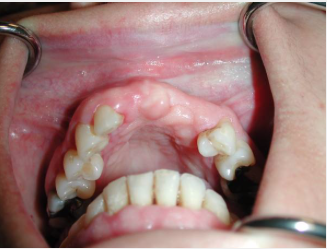

Lo schema con impianti inclinati nell'arcata mandibolare (inferiore) per evitare i forami mentali e ottenere in ogni caso un considerevole stabilità primaria per il carico immediato.

Le soluzioni più moderne rispetto al Toronto Bridge originale prevedono un trattamento abbastanza simile tra le due arcate. Gli impianti, se necessario, si inseriscono non paralleli tra loro ma con una inclinazione di circa 30° allo scopo di evitare i forami mentali nell'arcata inferiore e i seni mascellari nell'arcata superiore: l'obiettivo è ottenere una buona stabilità primaria degli impianti (necessaria anche per il carico immediato) anche in assenza di struttura idonea nelle zone posteriori evitando trattamenti più complessi con innesti di osso. Il posizionamento disparallelo/inclinato prevede necessariamente una componentistica del sistema implantare che permetta successivamente la protesizzazione degli impianti disparalleli. Infatti per gli impianti inclinati è prevista un protesizzazione con doppio moncone, un primo inclinato rispetto all'asse lungo dell'impianto (generalmente di 17°, 30° o addirittura 40-45°) ed un secondo in asse con l'emergenza del primo.